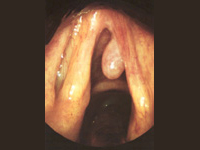

- Cirugía de Senos. Sólo si la medicación falla o la obstrucción nasal no se puede corregir con medicamentos, se puede considerar la cirugía. La cirugía endoscópica se recomienda para ciertos tipos de desórdenes sinusales. El endoscopio permite al cirujano ver directamente el interior de la nariz, y al mismo tiempo, eliminar tejidos y pólipos y limpiar los canales estrechos que hay entre los senos. La decisión de usar anestesia local o general se hará siempre de acuerdo con el paciente, dependiendo de sus circunstancias personales. Antes de la cirugía, usted ha de estar seguro que tiene expectativas realistas sobre los resultados, la recuperación y las curas postoperatorias. Los mejores resultados se obtienen, no sólo por el uso de técnicas sofisticadas, sino por el esfuerzo y la cooperación entre el paciente y el médico. Es igualmente importante que el paciente siga exactamente las instrucciones que le dé su médico antes y después de la intervención.